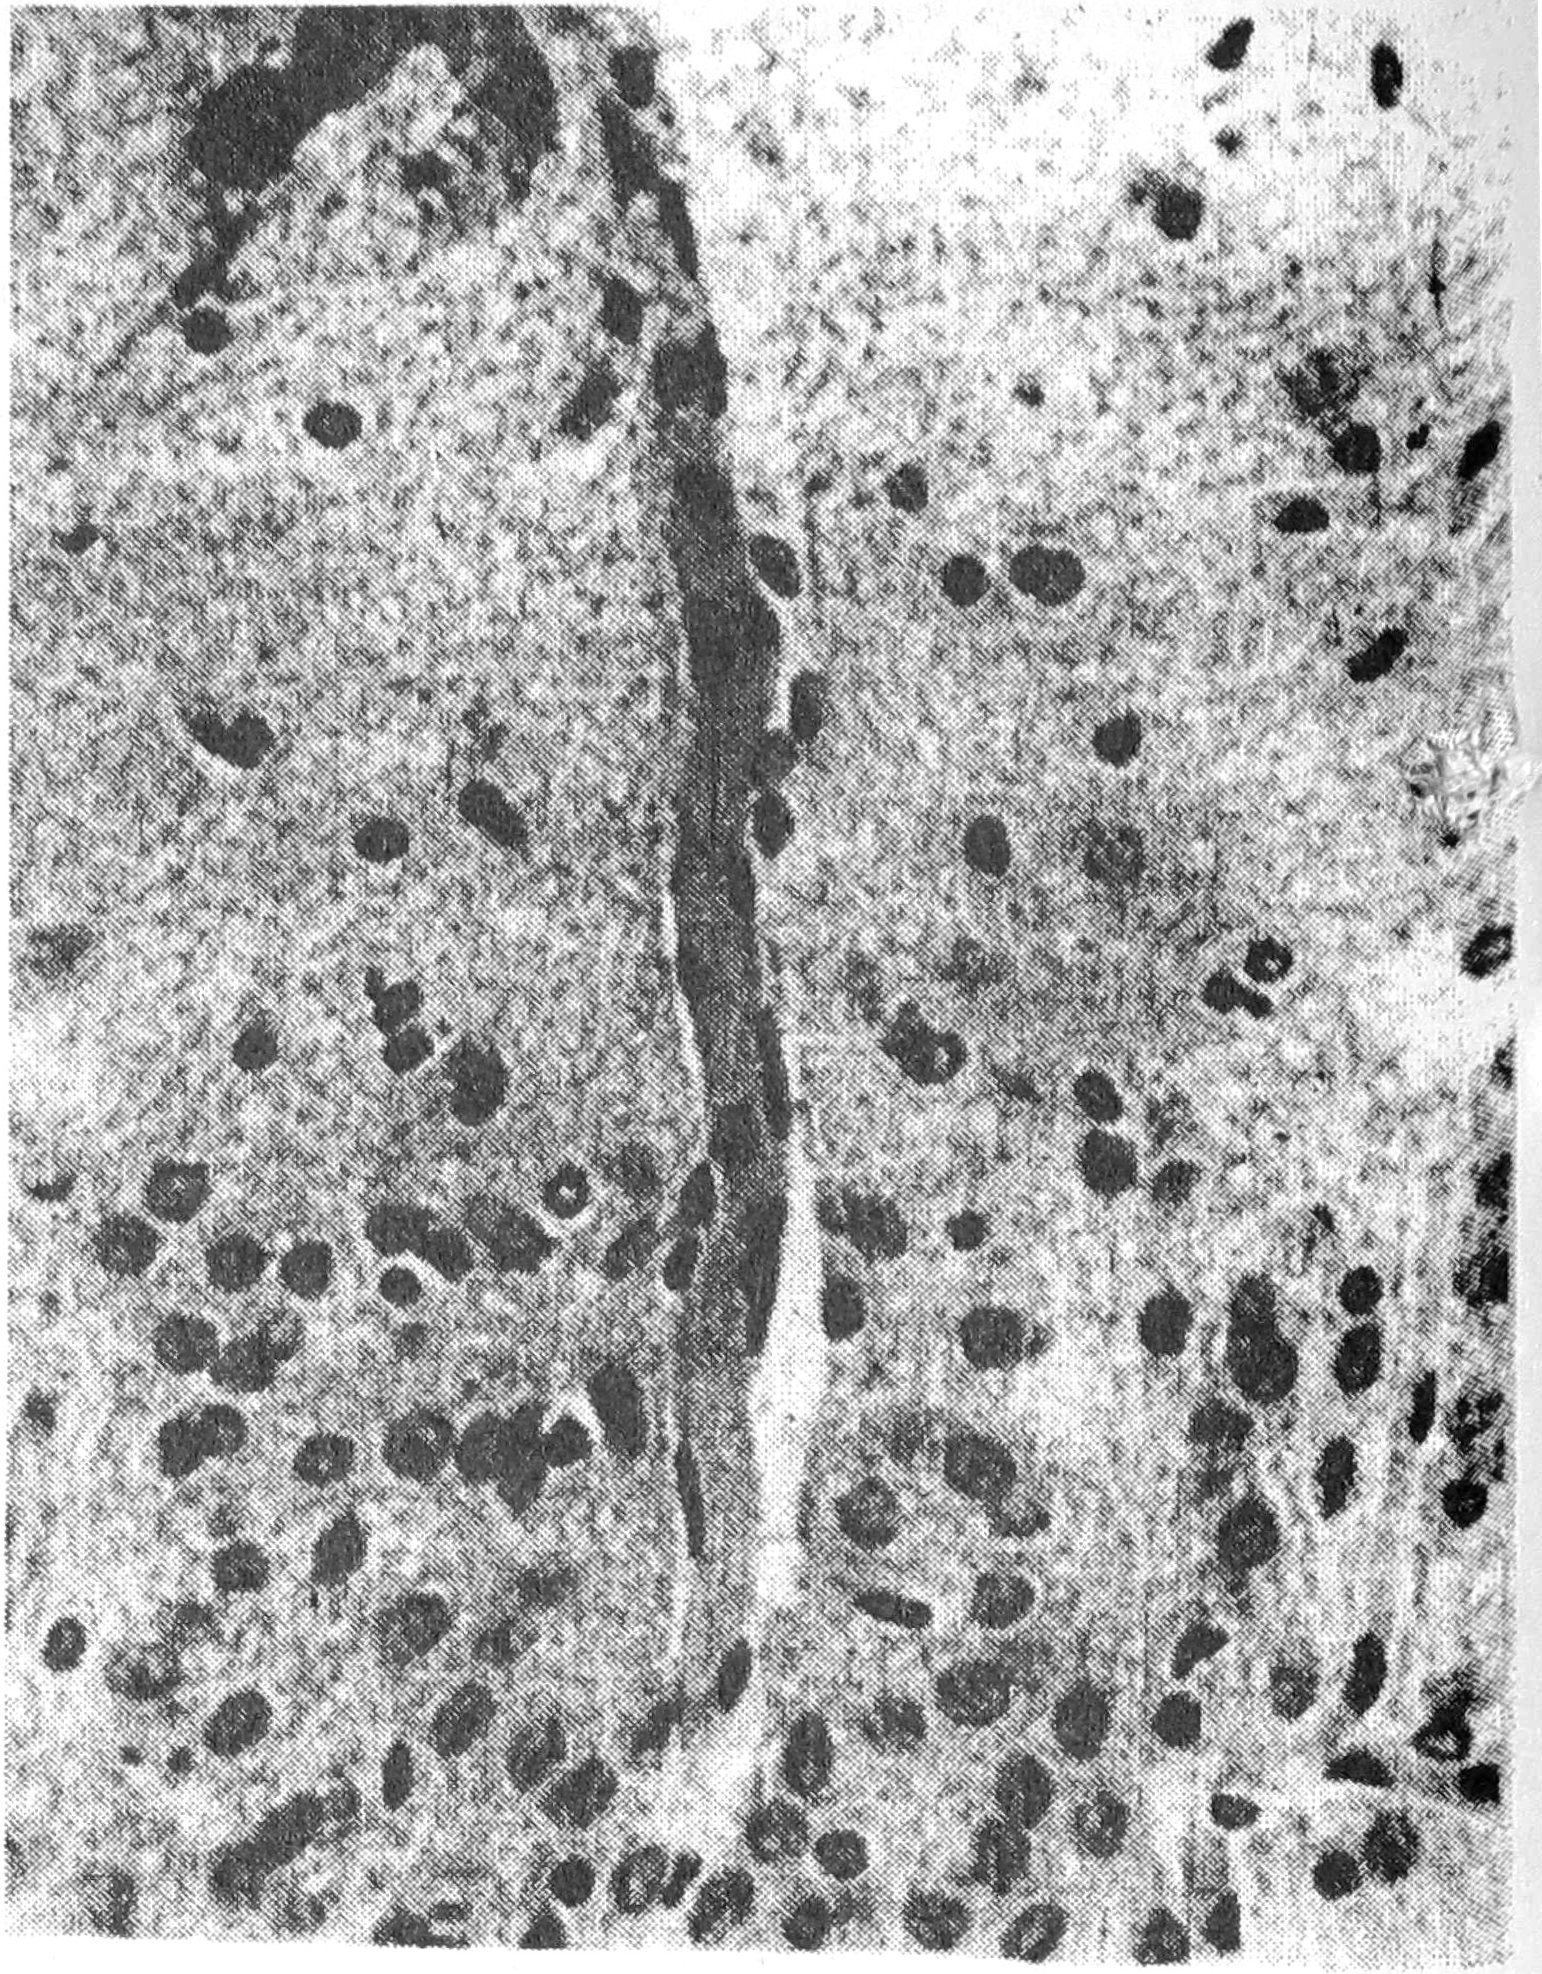

В значительной мере сходные изменения сосудов определялись через сутки после 4 аудиогенных припадков, возникших после перевязки левой общей сонной артерии (рис. 1).

Рис. 1. Набухание ядер эндотелия капилляра, периваскулярный отек сенсомоторной коры через 1 час после четырехкратных припадков нa фоне односторонней перевязки общей сонной артерии. Метод Ван Гизона. Ув. 10 х 20.